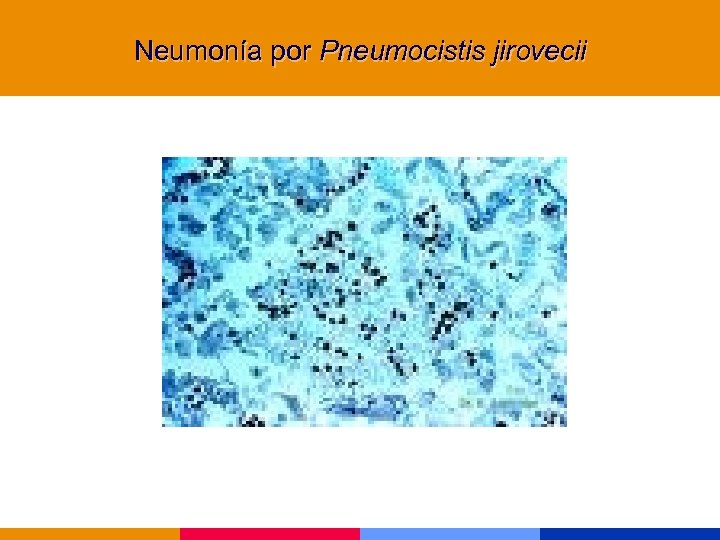

Neumonía por Pneumocistis jirovecii

Neumonía por Pneumocistis jirovecii

Neumonía por Pneumocistis jirovecii § CD 4 < 200 mm 3 § Comienzo insidioso: fiebre, tos seca, disnea. Hallazgos al examen físico incaracterísticos. § Lab: VSG: 50 mm. LDH, valor diagnóstico y pronóstico. Hipoxemia. § Rx infiltrado intersticial difuso, neumatocele, neumotórax. § TC de alta resolución.

Neumonía por Pneumocistis jirovecii § CD 4 < 200 mm 3 § Comienzo insidioso: fiebre, tos seca, disnea. Hallazgos al examen físico incaracterísticos. § Lab: VSG: 50 mm. LDH, valor diagnóstico y pronóstico. Hipoxemia. § Rx infiltrado intersticial difuso, neumatocele, neumotórax. § TC de alta resolución.